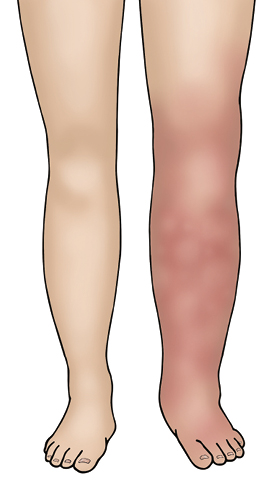

DVT – Symptoms can include:

- swelling

- redness/discolouration

- warmth

- tenderness/pain of the legs that may be worse when standing or walking. Occasionally, there are no symptoms except pain.